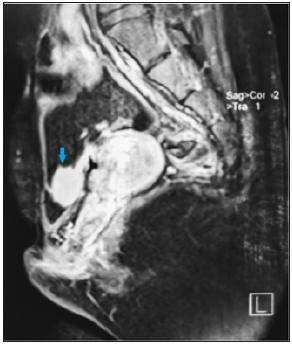

A 21-year-old woman with history of bladder extrophy, for which she had undergone an enterocystoplasty with bladder enlargement and mitrofanoff type bypass; She is under intermittent catheterization since the age of 6, and a vaginal reconstruction with labioplasty is planned for her; the patient presented with a one-year history of recurrent urinary tract infections, difficult self-catherization and a pelvic heaviness. The operative details of all her surgeries were not available to us. A pelvic MRI was performed, as part of surveillance, revealing a large neo-bladder calculi measuring 27x15mm (Figures 1-3), ultrasound has shown no renal lithiasis or hydronephrosis and the creatinine clearance was normal (49μmol/l), the calculi was radio-opaque on X-ray abdomen (Figure 1). Physical examination of her abdominopelvic region revealed multiple scars, a catheterizable stoma, and an ablated urethra (Figure 2).

Figure 3:MRI showing a large bladder calculi (27x15mm).